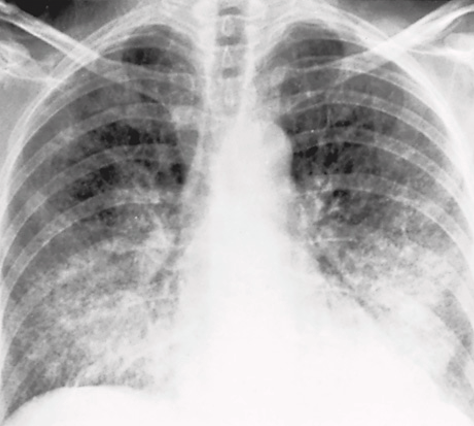

miliary tuberculosis

COVID-19